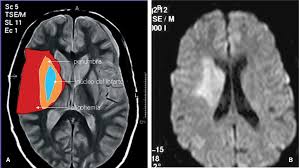

Entenda como essa técnica detecta precocemente AVCs, tumores e lesões cerebrais.

Saiba mais